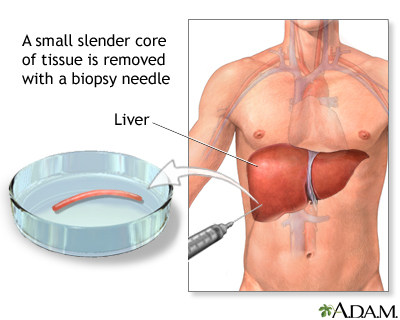

- Liver biopsy